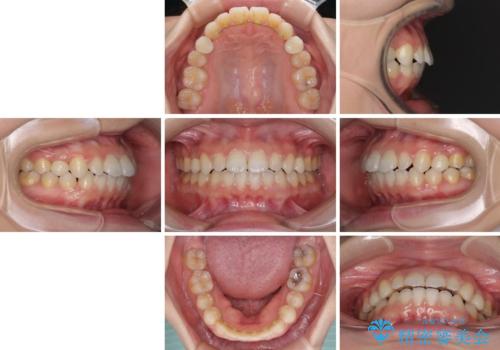

- 歯の欠損による隙間だらけの歯並びを気にして来院された患者様です。

上顎左右1本ずつ欠損していたため、歯列矯正により欠損部位にスペースを集め、その後欠損部位をインプラントにて補綴することとしました。

インビザラインによる矯正治療も提案しましたが、長時間の装着や自己管理が難しいとお考えで、ワイヤーによる矯正治療を行いました。

歯並びは比較的早めに整いましたが、インプラントを埋入するにあたって前後の歯根位置を改善する必要があり、矯正治療に期間を要することとなりました。